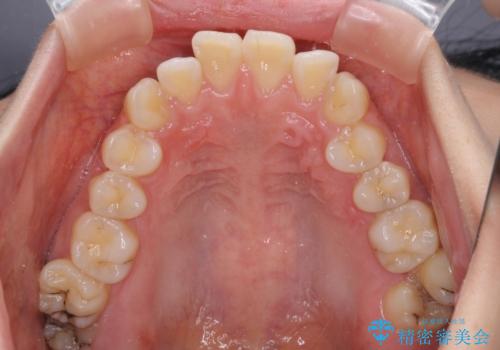

- 前歯のデコボコや口元の突出感、口の閉じにくさを気にして来院された患者様です。

上下左右第一小臼歯4本を抜歯し、ワイヤー装置にてデコボコを解消しながら口元を引っ込めるよう矯正治療を行うこととしました。

抜歯スペースを閉じている過程で、左側の上下犬歯が引っかかってしまい、進捗が停滞しましたが、当初予定の2年~2年半の間で無事に治療を終えることができました。